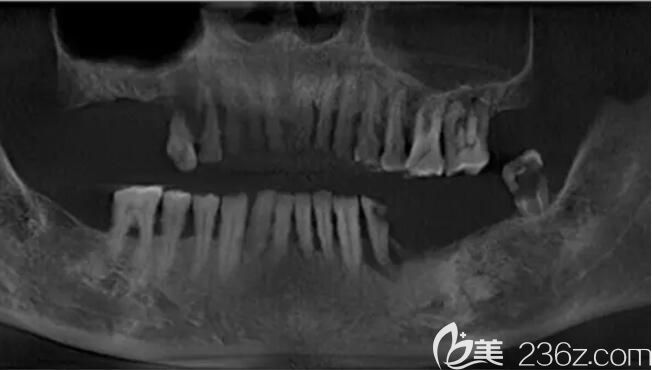

▲种植术前检查、CT拍片

经过检查,发现卢老先生上、下颌牙共缺失11颗。